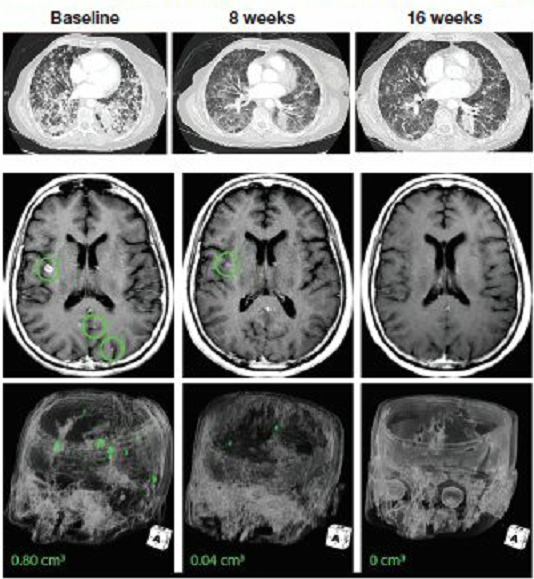

02、肺癌脑转移:一线治疗,脑部肿瘤几乎全部消失

一位78岁的女性既往没有接受过任何治疗的晚期肺癌患者,确诊时已经出现了严重的脑转移,拒绝接受化疗,基因检测后发现存在EPS15-NTRK融合。接受拉罗替尼治疗后,肺部的病灶缩小了34%。脑部的转移灶几乎全部消失(减少95%)。